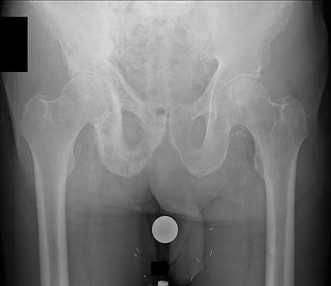

Question 1

A 12-year-old obese boy presents with vague left thigh and knee pain. He is diagnosed with a Slipped Capital Femoral Epiphysis (SCFE) as seen in similar clinical scenarios.

During percutaneous in-situ fixation, unrecognized penetration of the guide wire into the hip joint occurs. What is the most likely specific complication resulting from this technical error?

Explanation

Chondrolysis is a severe complication of SCFE characterized by rapid destruction of the articular cartilage. While it can occur idiopathically, its most established iatrogenic cause is unrecognized intra-articular hardware penetration. The 'approach-withdraw' fluoroscopic technique is required during pinning to assure pins are entirely intraosseous. Avascular necrosis (AVN) is usually due to damage to the epiphyseal blood supply (retinacular vessels) secondary to the initial displacement, forceful closed reduction, or posterosuperior pin placement.